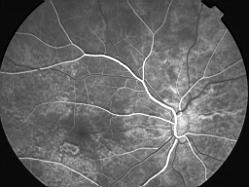

ASSOCIATION STRIES ANGIOIDES ET DYSROPHIE MACULAIRE RETICULEE

NEOVASCULARISATION